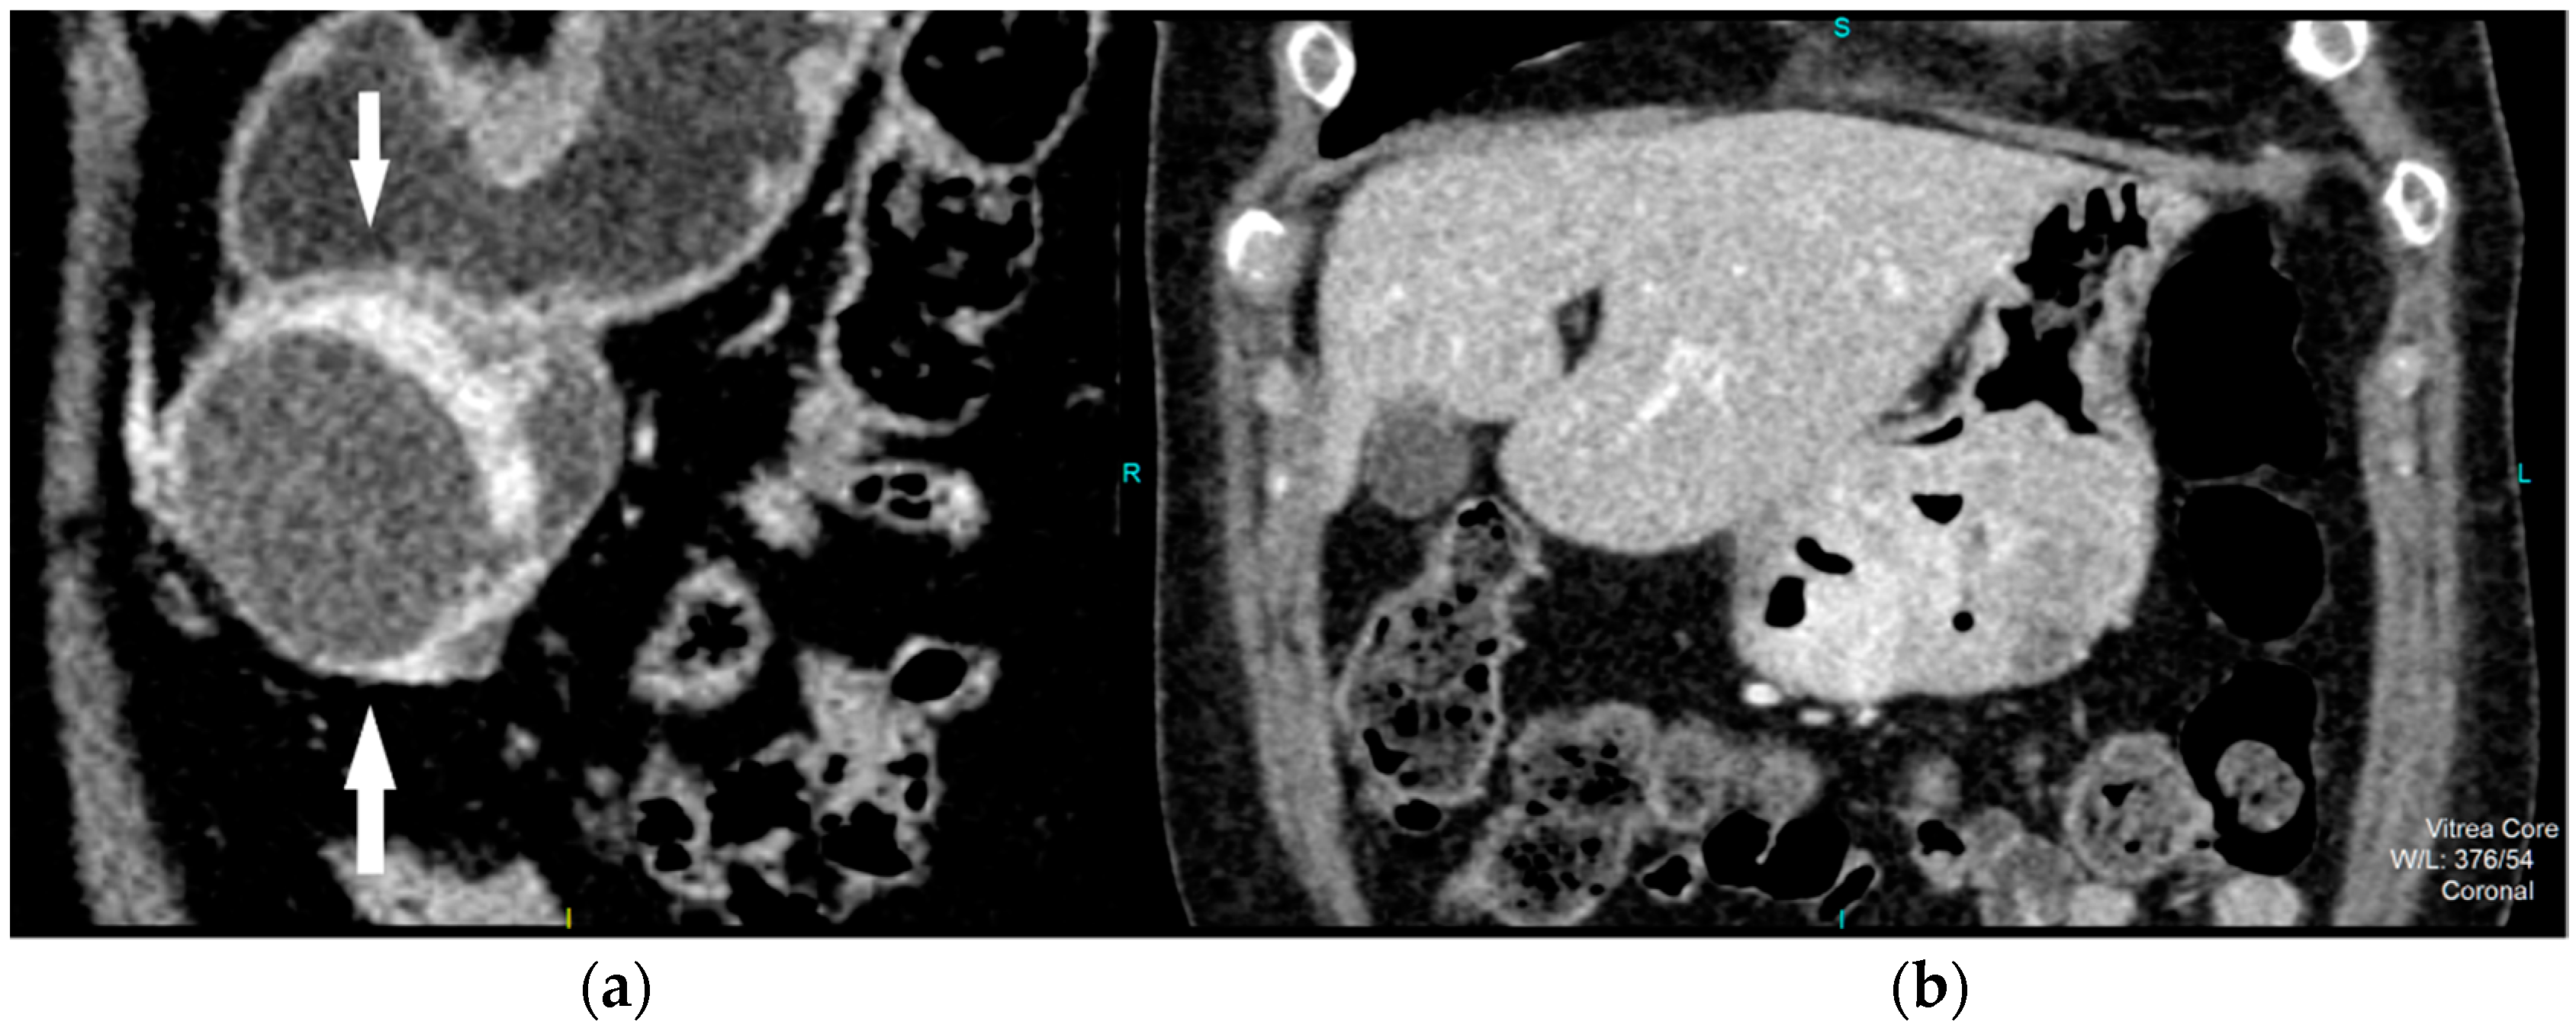

Figure 2.

Contrast enhanced CT, coronal view, shows high risk GIST in a 69-year-old female patient, with a clearly demarcated submucosal lesion in the antrum of the stomach with an exophytic growth pattern and predominantly cystic structure with the strong post-contrast enhancement of solid part of tumor (arrows) (a). CT examination, coronal section, in a 49-year old female patient reveals intraluminal predominantly solid tumor lesion with irregular shape and margins, endophytic growth with the discontinuity of gastric mucosa and obvious post-contrast enhancement in a HR GIST (b).

Figure 3.

Contrast enhanced CT exam, coronal view, in a 49-year old female patient shows irregular shape and EFDV (white arrow) of a HR GIST.